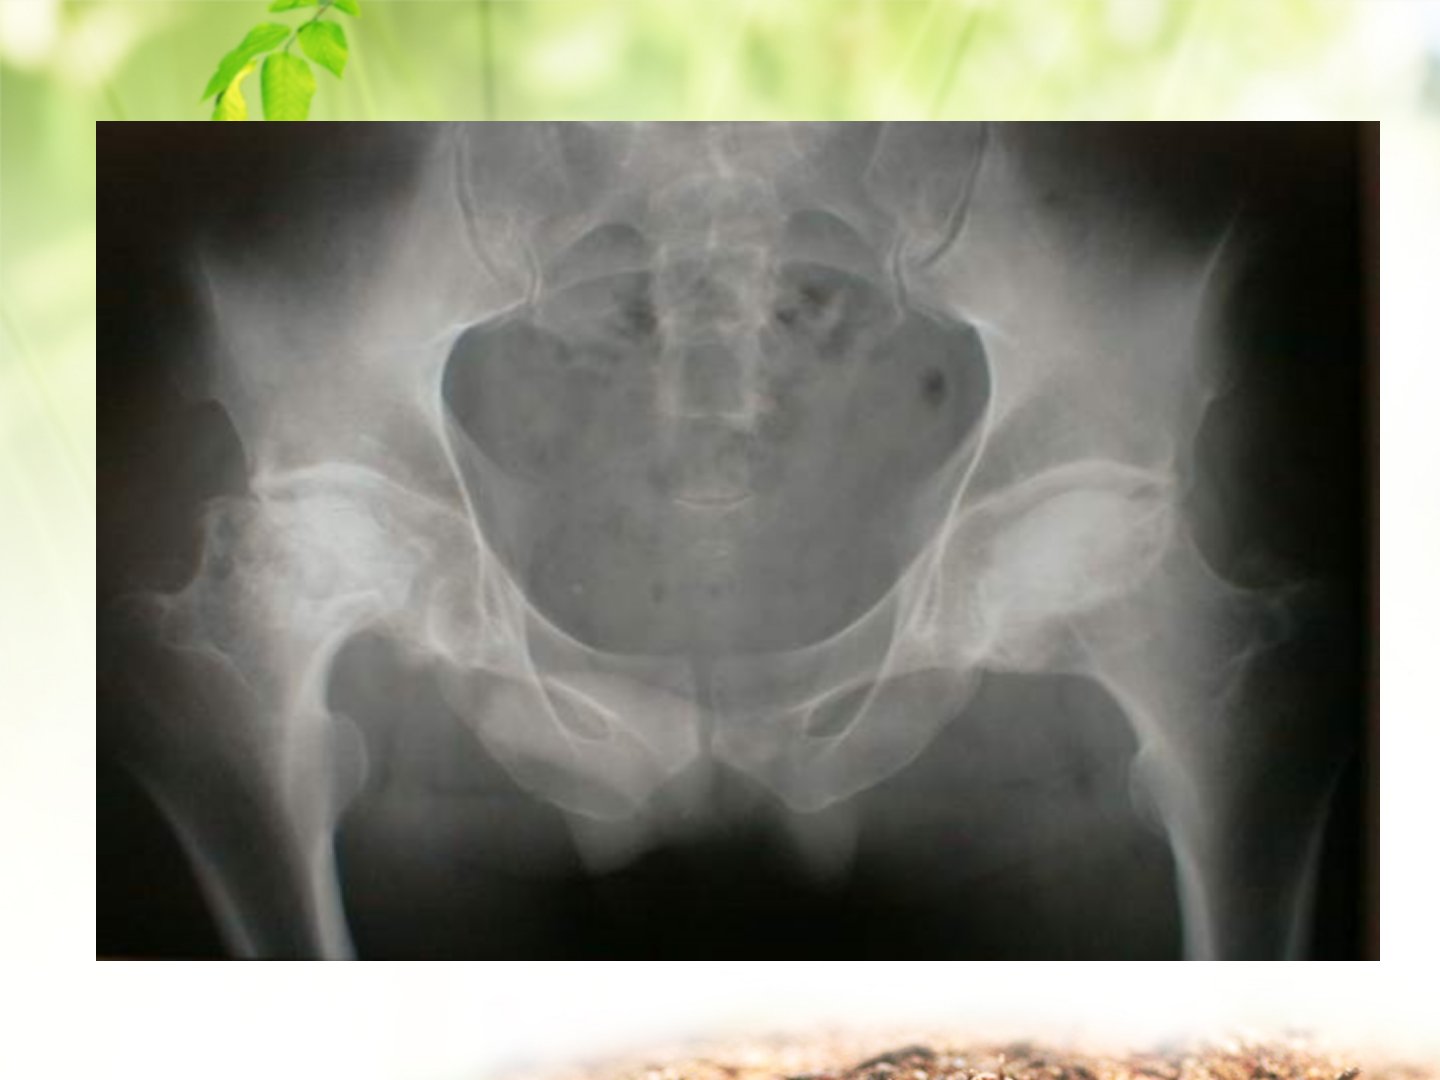

《WELCOME股骨头坏死的治疗与护理》摘要本文由协和医院骨科宋红燕分享旨在让学习者掌握股骨头坏死术后护理要点熟悉股骨头置换术的适应证、禁忌证与并发症了解术后康复训练。骨坏死是骨细胞等有活力成分因多种因素坏死的病理过程以股骨头最常见。病因包括创伤、疾病、药物及不良生活习惯等。其病理变化是血液循环障碍致骨坏死与修复交织最终可致股骨头塌陷及髋关节退行性关节炎。诊断有主要标准和次要标准两个或以上主要标准阳性可确诊一个主要标准阳性或三个次要标准阳性(至少一个X线片阳性改变)可诊断为可能坏死。临床表现多样好发于2050岁男性有疼痛、关节僵硬等症状。治疗上不同时期选择不同方式如细针髓心减压、自体骨髓干细胞移植等严重者行人工关节置换术。置换术有适应证与禁忌证。术前护理要关注患者心理等问题并采取相应措施术后需观察病情、做好体位护理等预防并发症。术后康复分阶段进行从肌肉静力收缩到逐步增加关节活动度。出院后要注意训练强度、行走辅助工具使用遵循“6不要”完全康复后可进行适当体育活动。